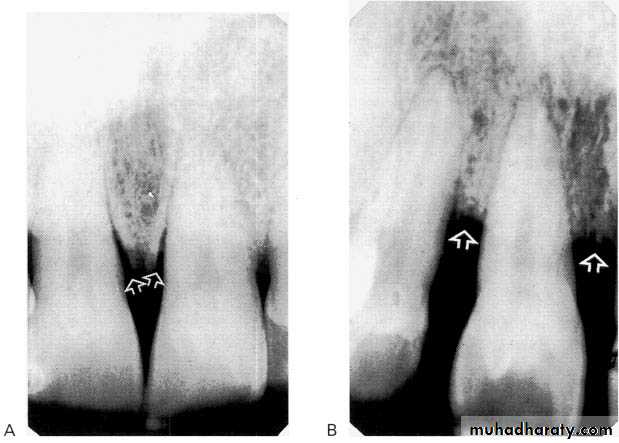

Bone loss

• Severity: classified to

Mild bone loss: crestal changes (The anterior regions show blunting of the alveolar crests and slight loss of alveolar bone height.Posteriorly show loss of the normally sharp angle between the lamina dura and alveolar crest).

• Moderate bone loss: bone loss of 10-33%.

• Severe bone loss: bone loss of 33% or more.

A:moderate,B:sever.